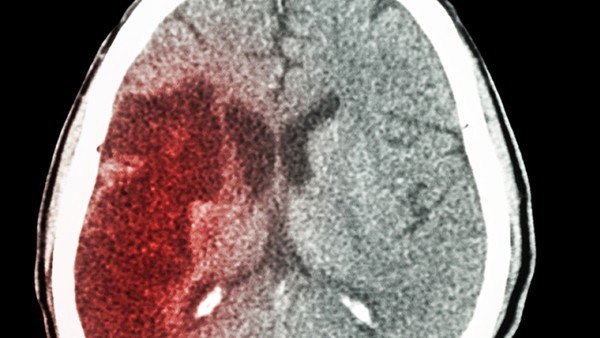

高血压这种不良症状的出现,通常跟患者长期精神紧张以及经常生气,还有高脂肪以及高盐饮食,还包括喝酒以及睡眠不好等等不良生活习惯有很大的关系。高血压这种不良症状必须及时治疗,否则容易诱发心脑供血不足,继而诱发冠心病以及脑中风等等足以致命的后果发生。